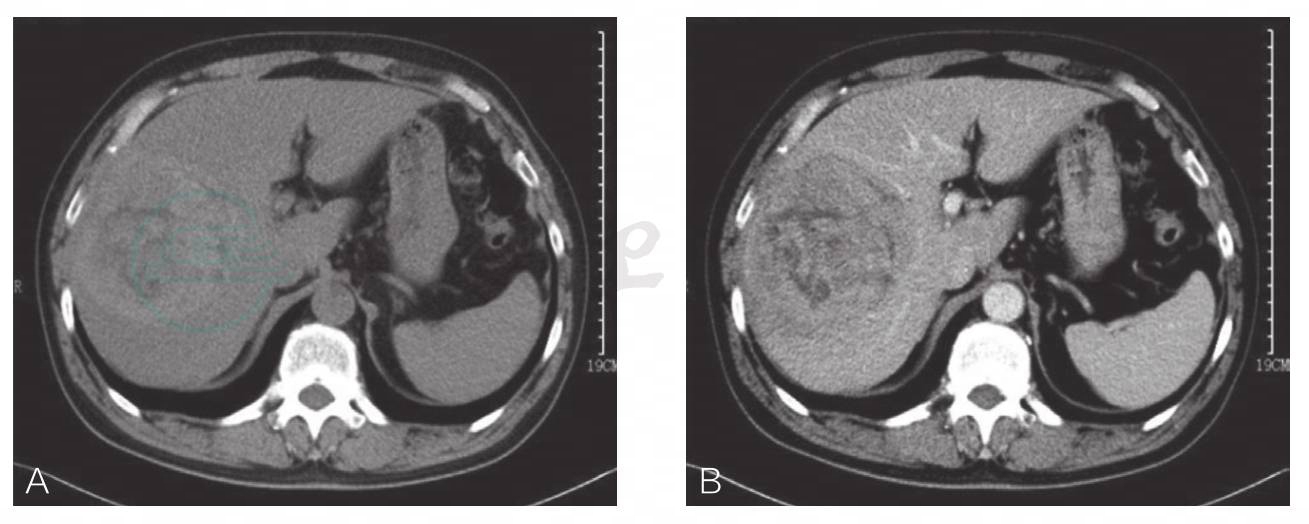

腹部CT检查:右肝巨大占位,原发性肝癌首先考虑(图1)。

图1 右肝巨大占位,原发性肝癌首先考虑